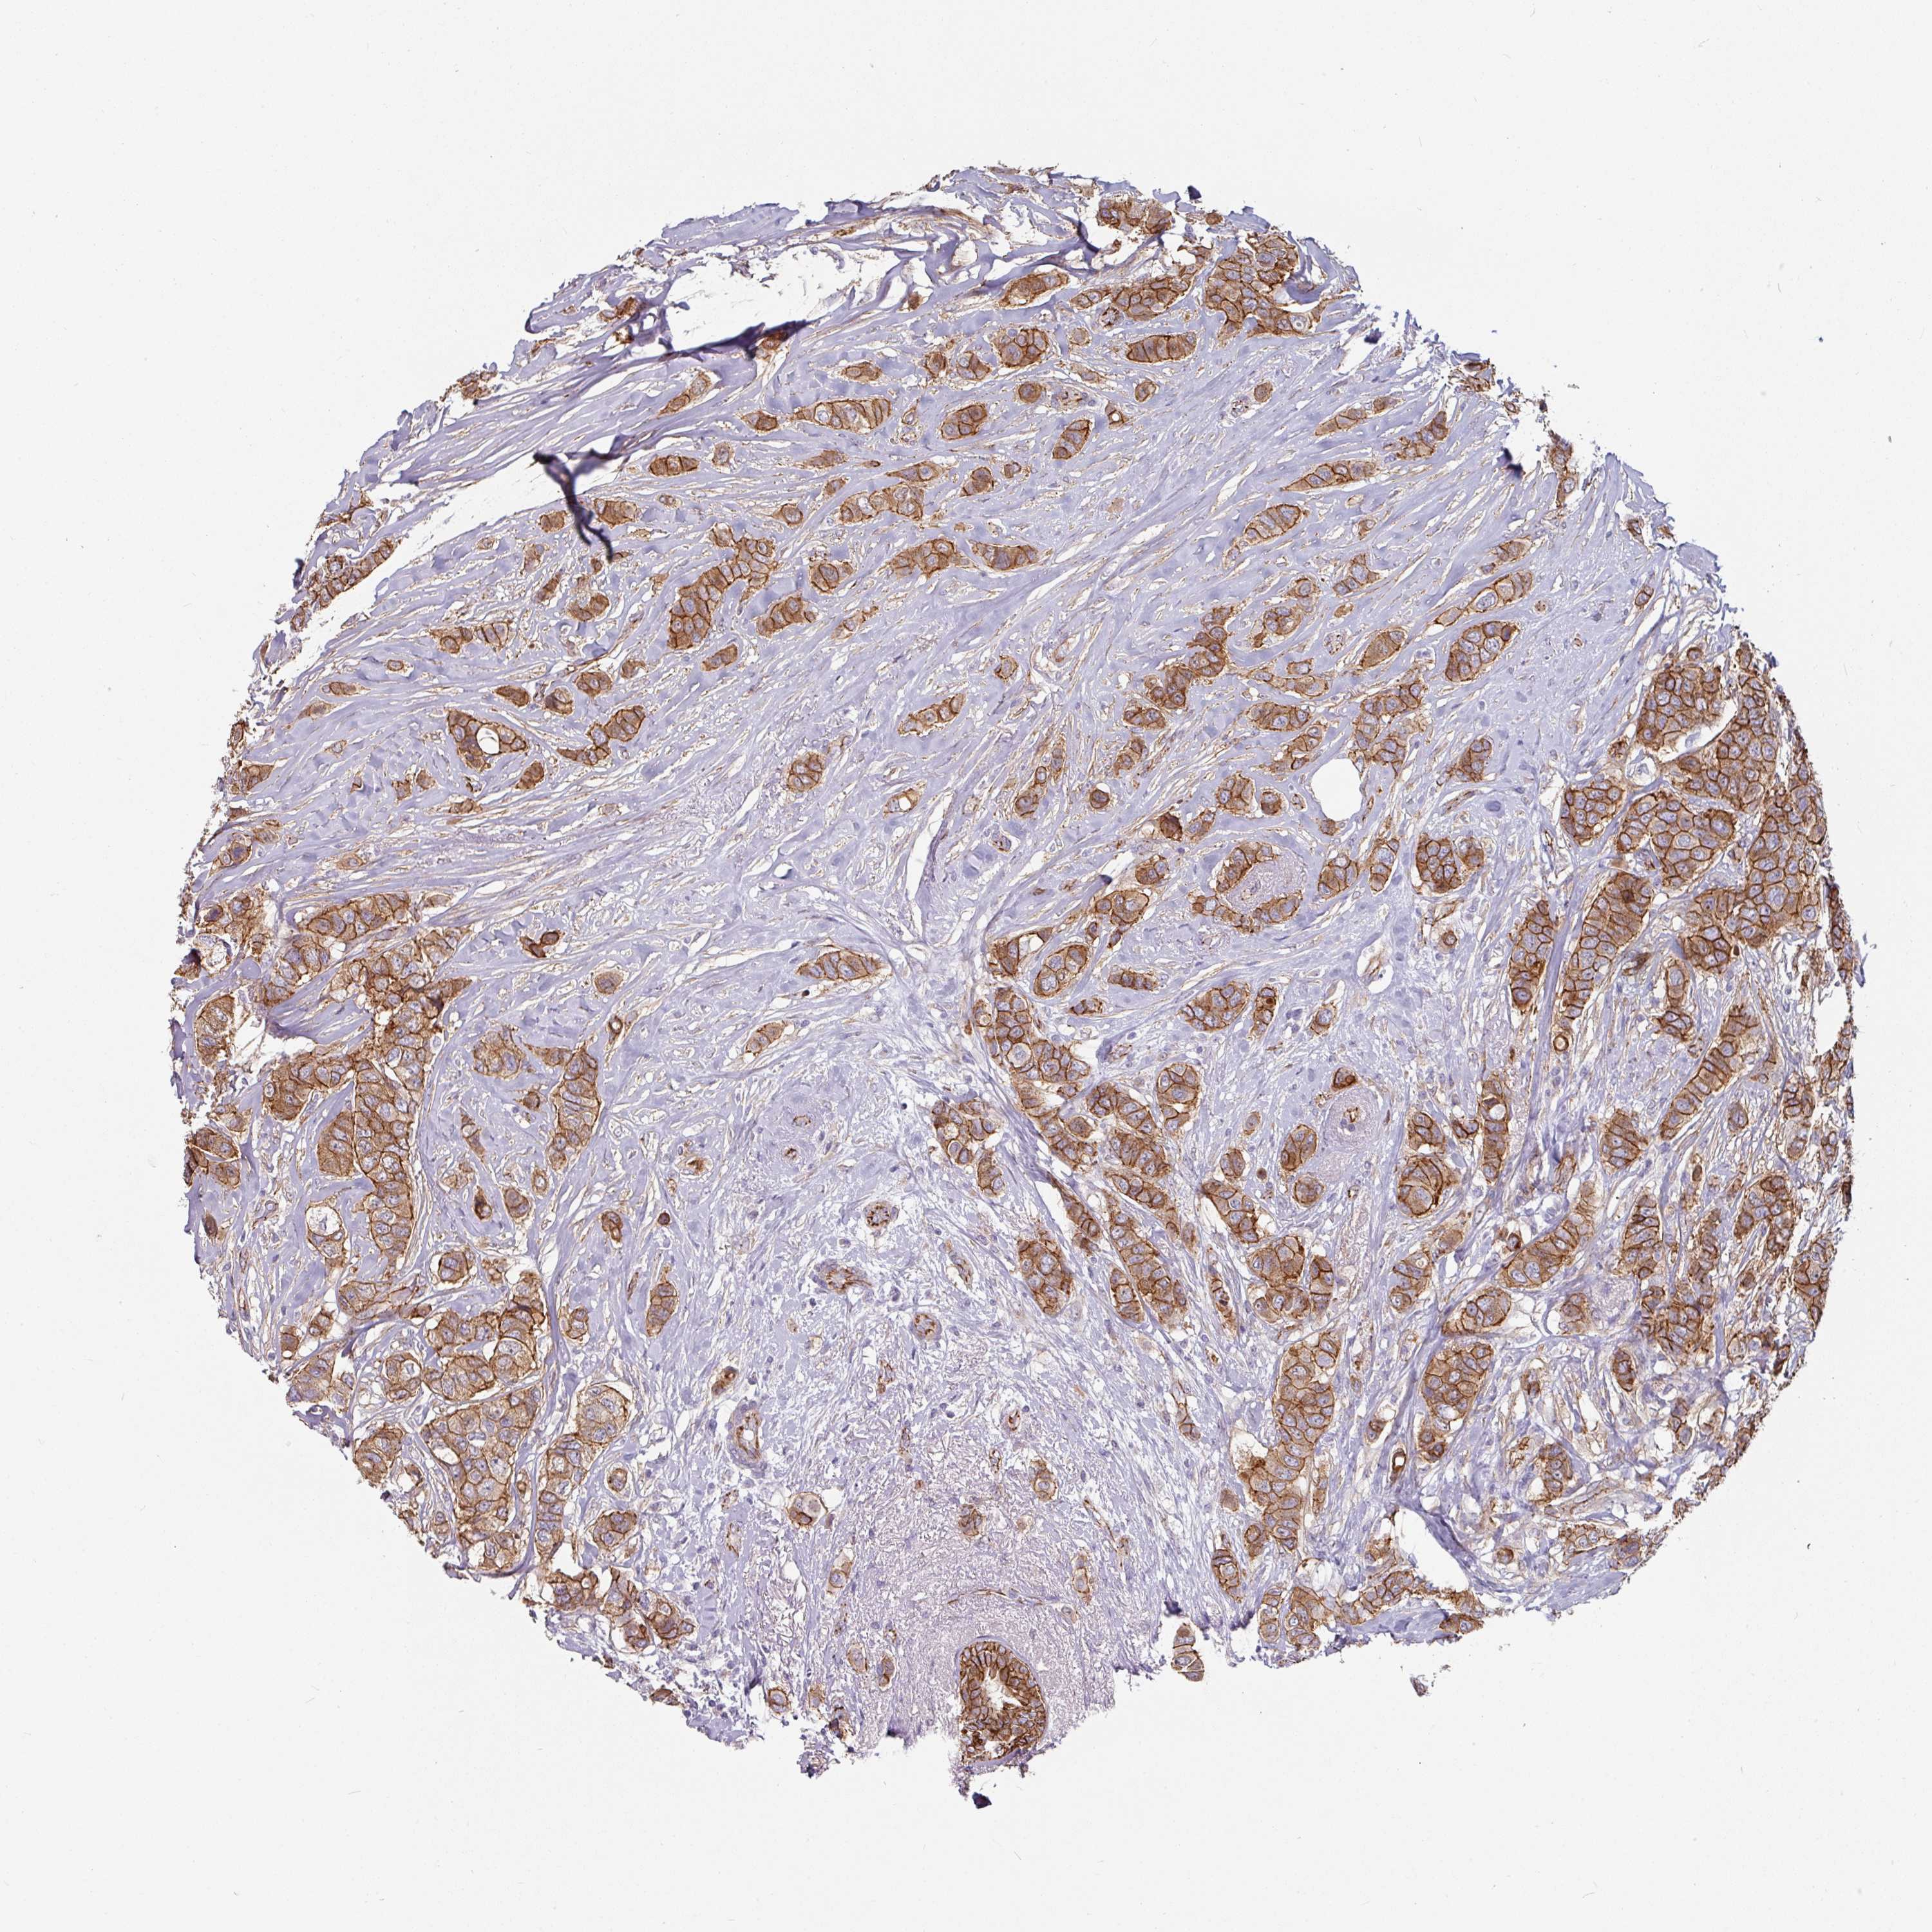

BRCA TCGA BRCA VALIDATION PROTEIN EXPRESSION

ANTIBODIES

AND

VALIDATION